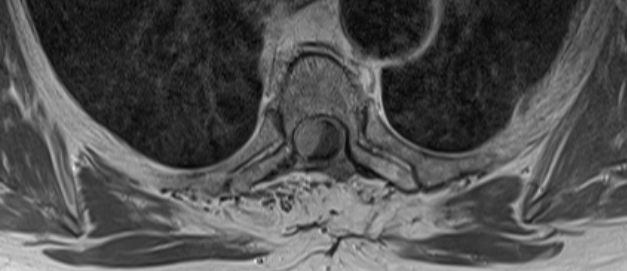

| Rückenmark |

76-jährige Frau mit Rezidiv eines Rückenmarks-Meningeoms. Erstmanifestation vor 17 Jahren. Rezidive von 12, 6 und 3 Jahren jeweils operativ beherrscht. Seit einem Jahr erneut Schmerzen zwischen den Schulterblättern und Druckgefühl im Thoraxbereich. Reduzierter AZ und adipöser EZ. KHK, VHF, Hypertonie, Hypothyreose. Auf Rollator angewiesen. Zunehmende Gangunsicherheit und Kribbeln in den Beinen. Klopfschmerz im Bereich von BWK2-5 stark auslösbar. Die Schmerzen strahlen zeitweise in die Schulterblätter aus. | ![]() | |||||